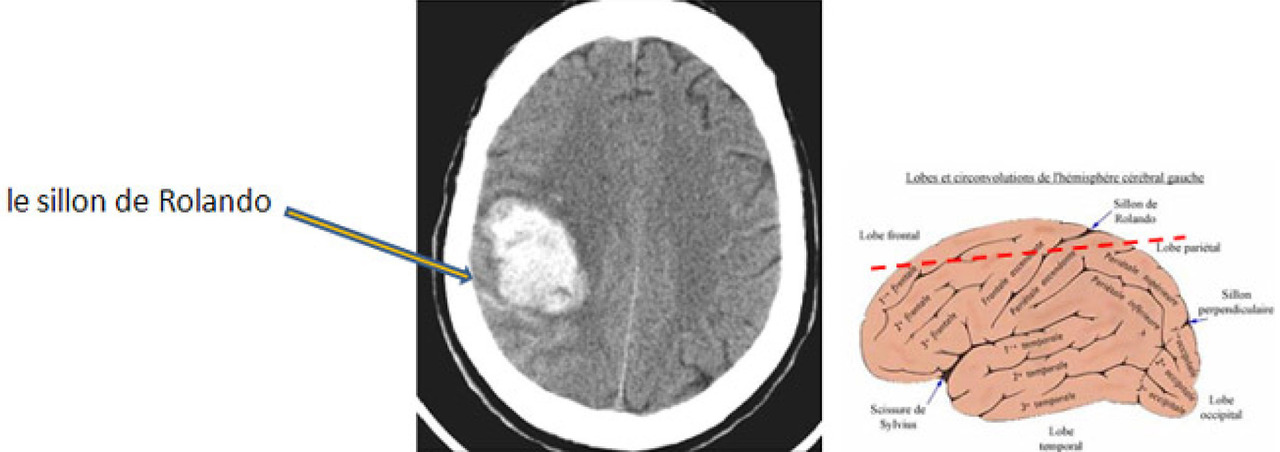

Il s’agit d’un hématome cortical sur une coupe TDM cérébrale sans injection. L’hémorragie apparaît comme une zone spontanément hyperdense. Ici il s’agit d’une hyperdensité spontanée frontale droite. Il s'agit bien d'un hématome frontal car en avant du sillon de Rolando, qui, sur des coupes axiales, souvent obliques, est en général situé assez en arrière sur ces coupes hautes.